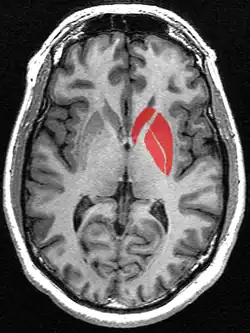

The striatum as seen on MRI. The striatum includes the caudate nucleus and the lentiform nucleus which includes the putamen and the globus pallidus

The striatum in red as seen on MRI. The striatum includes the caudate nucleus (top), and the lentiform nucleus (the putamen (right) and the globus pallidus (lower left))